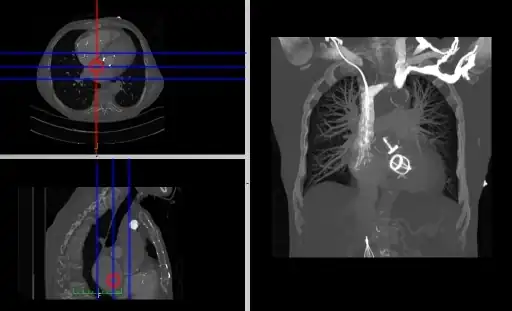

- Coronal and sagittal reconstructions are referred to as Orthogonal MPRs because the perspectives generated are from planes of image data which are at right angles to each other. Composite MPR displays can be generated so that linked cursors or crosshairs can be used to locate a point of interest from all three perspectives, as illustrated in these images:

![]() |

- This form of image presentation is sometimes referred to as a TCS display – implying the viewing of Transaxial, Coronal and Sagittal slices. It can be combined with the slice projection methods we discussed earlier, as illustrated in the two sets of images below, where the blue lines highlight the limits of the coronal projections: